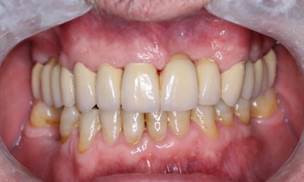

Se inició el tratamiento con la prótesis fija completa superior en forma de herradura realizando tallado de las piezas dentarias superiores sin endodoncia previa, utilizando anestesia local mepivacaina sin vasoconstrictor, colocando provisionales posteriormente; luego se continuó a tomar impresión definitiva para realizar con el laboratorio la estructura metálica posteriormente realizando prueba de ésta a la siguiente cita, se realizó cementación final de la prótesis realizando una rehabilitación completa definitiva en el sector superior (Figura 3).